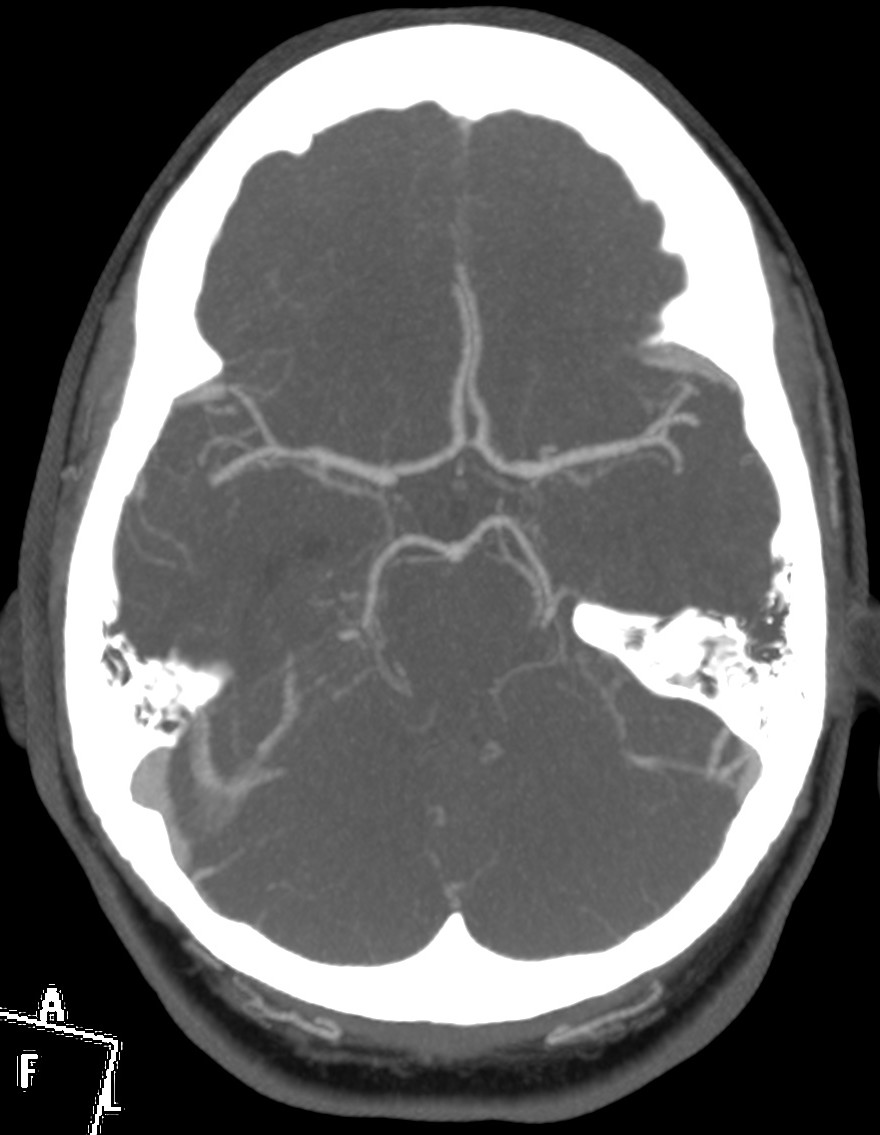

Se decide ingreso de la paciente para estudio y, ante el incremento de la cefalea y empeoramiento del estado general, se realiza nuevo TC de cráneo sin contraste. Veámos las imágenes.

1- TAC SIN CONTRASTE:

Se realiza para descartar otros procesos como infartos, tumores o infecciones.

- Signos directos: Cuerda Hiperdensa. En caso de trombo en las venas corticales, se observa el signo de la cuerda hiperdensa intraluminal. El trombo puede permancer hiperdenso 2 semanas para luego hacerse isodenso. La S y E de este signo son bajas.

- Signos indirectos: Cambios en el parénquima debido a la isquemia por perturbación del flujo venoso, produciéndose edema, infartos o hemorragias. Los infartos no hemorrágicos son las lesiones más frecuentes, suelen ser de localización subcortical, no sigue una distribución arterial y se localiza en las inmediaciones del seno afectado. Una afectación del SSS (el más frecuente) produce afectación bilateral en los territorios frontales, parietales y occipitales. Una afectación del ST afecta los lóbulos temporales. El seno recto afectado produce lesión profunda, en el tálamo. Los infartos hemorrágicos son menos frecuentes, se han descrito sangrados subdurales, subaracnoideos e incluso abiertos a ventrículos. El edema que se produce puede originar efecto masa con desplazamiento de la línea media e incluso disminución de ventrículos (dificil de valorar en jóvenes). La hidrocefalia marcada no se suele producir.